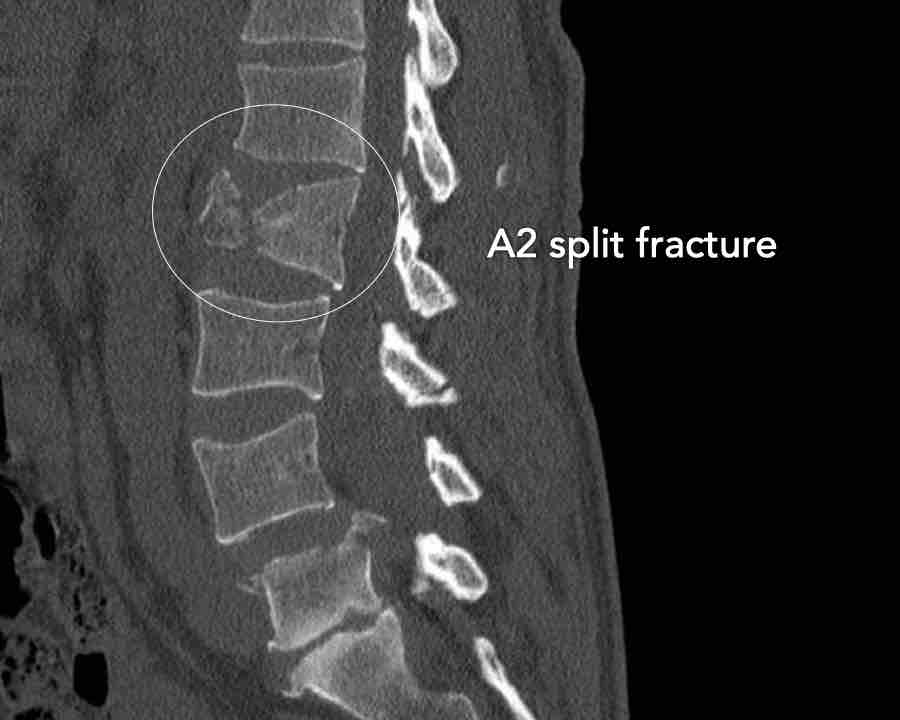

A2 Split fracture

A2 is a fracture of both endplates without involvement of the posterior wall of the vertebral body.

What is the highest AO-type of injury?

Findings:

- No C or B injury

- Fracture of the vertebral body with involvement of both endplates (1+1 points), no posterior wall involvement

Conclusion

injury type A2